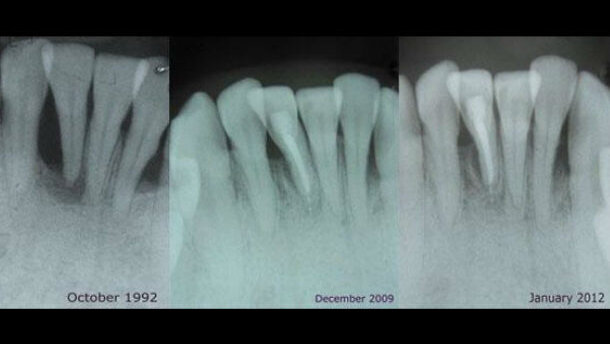

Un uomo di 21 anni si presenta con un importante disturbo dovuto a una ricaduta di un trattamento ortodontico effettuato durante l’adolescenza. Ha ...